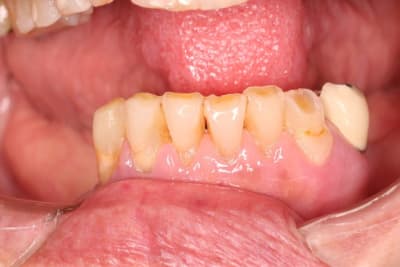

Le bas, on garde ou on vire ? 34 mobile, le reste ça bouge pas.

sinon pour le bas je vire pas si le patient en fait pas la demande ou ne signe pas pour au moins des locator.

Oui , aller,,on garde le bas qui nous servira de repère pour faire le haut

Je garderai tout ce qui ne bouge pas en bas. Virer des dents immobiles et asymptomatiques c'est sévère ! ;) Un bon bloc d'ancrage pour le stellite.

de toute facon , le stellite ne servira pas de calage , il sera tres tres vite en sous occ . avec un joli crochet qui va flotter , donc autant faire un crochet bien souple .

je pense que c est plus l'occlusion qui finira les canines , sauf si CCAM en bas aussi .

ils augmenteraient l'asialie ,du coup ,les dents s'useraient a grande vitesse par manque de lubrification .ce qui pourrait aussi expliquer l'etat du haut et des gencives ......